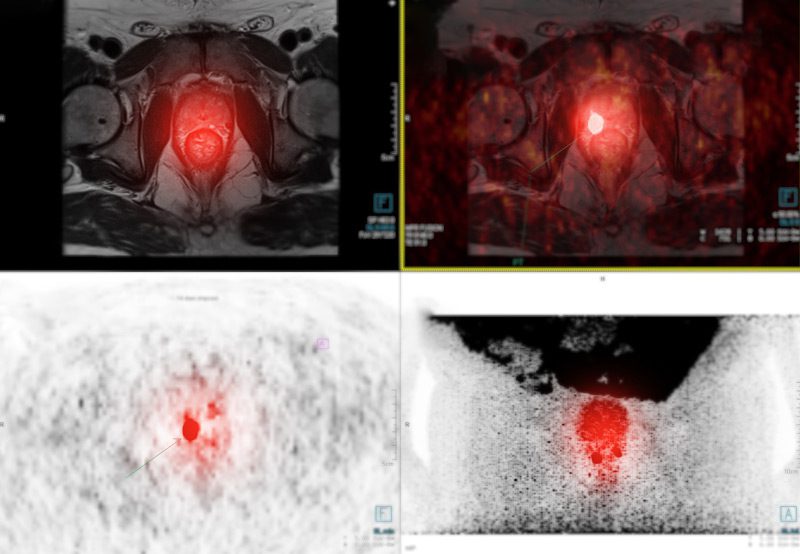

Advanced imaging techniques like PSMA PET and multiparametric MRI (mpMRI) are transforming the way prostate cancer is diagnosed, staged, and monitored. These tools offer far greater accuracy than conventional imaging, allowing for more precise treatment decisions and better outcomes.

Prostate-specific membrane antigen positron emission tomography (PSMA PET) is a cutting-edge imaging modality that detects prostate cancer cells using a radiotracer that binds to PSMA—a protein found in high levels on prostate cancer cells. After the tracer is injected, a PET scan highlights cancerous areas with remarkable clarity.

Compared to conventional CT or bone scans, PSMA PET detects cancer spread earlier and with higher sensitivity, helping tailor treatments to the exact extent of disease.

Multiparametric MRI combines anatomical and functional imaging to visualize prostate tumors in high resolution. It assesses prostate tissue using various MRI sequences, including T2-weighted imaging, diffusion-weighted imaging, and dynamic contrast enhancement.